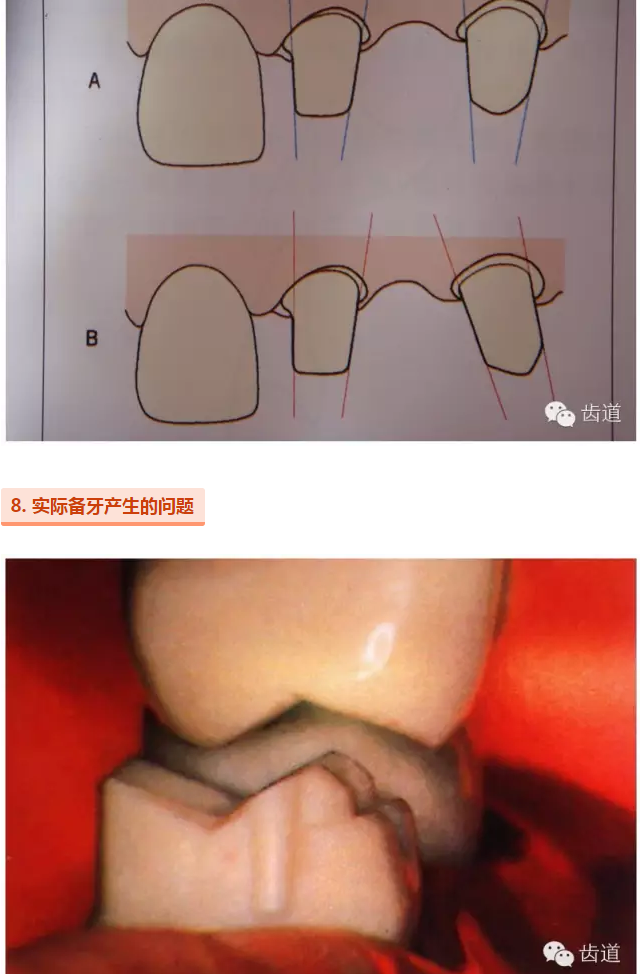

l多個基牙時就位道的調(diào)節(jié)

l實際備牙產(chǎn)生的問題

牙的外形及洞形的幾何形狀:主要是牙體制備出一定聚合角度產(chǎn)生的阻擋作用